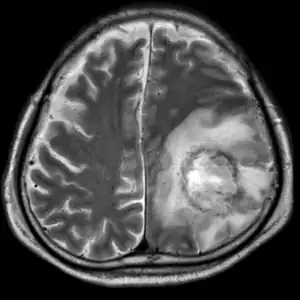

| T2-weighted MRI showing liquefied, necrotic brain tissue as a result of GAE caused by an infection of Acanthamoeba, genotype T18 | |

Granulomatous amoebic encephalitis (GAE)[2] is a rare, usually fatal, subacute-to-chronic central nervous system disease caused by certain species of free-living amoebae[3] of the genera Acanthamoeba, Balamuthia and Sappinia.[4][5] The term is most commonly used with Acanthamoeba. In more modern references, the term "balamuthia amoebic encephalitis" (BAE) is commonly used when Balamuthia mandrillaris is the cause.[6][7][8][9]